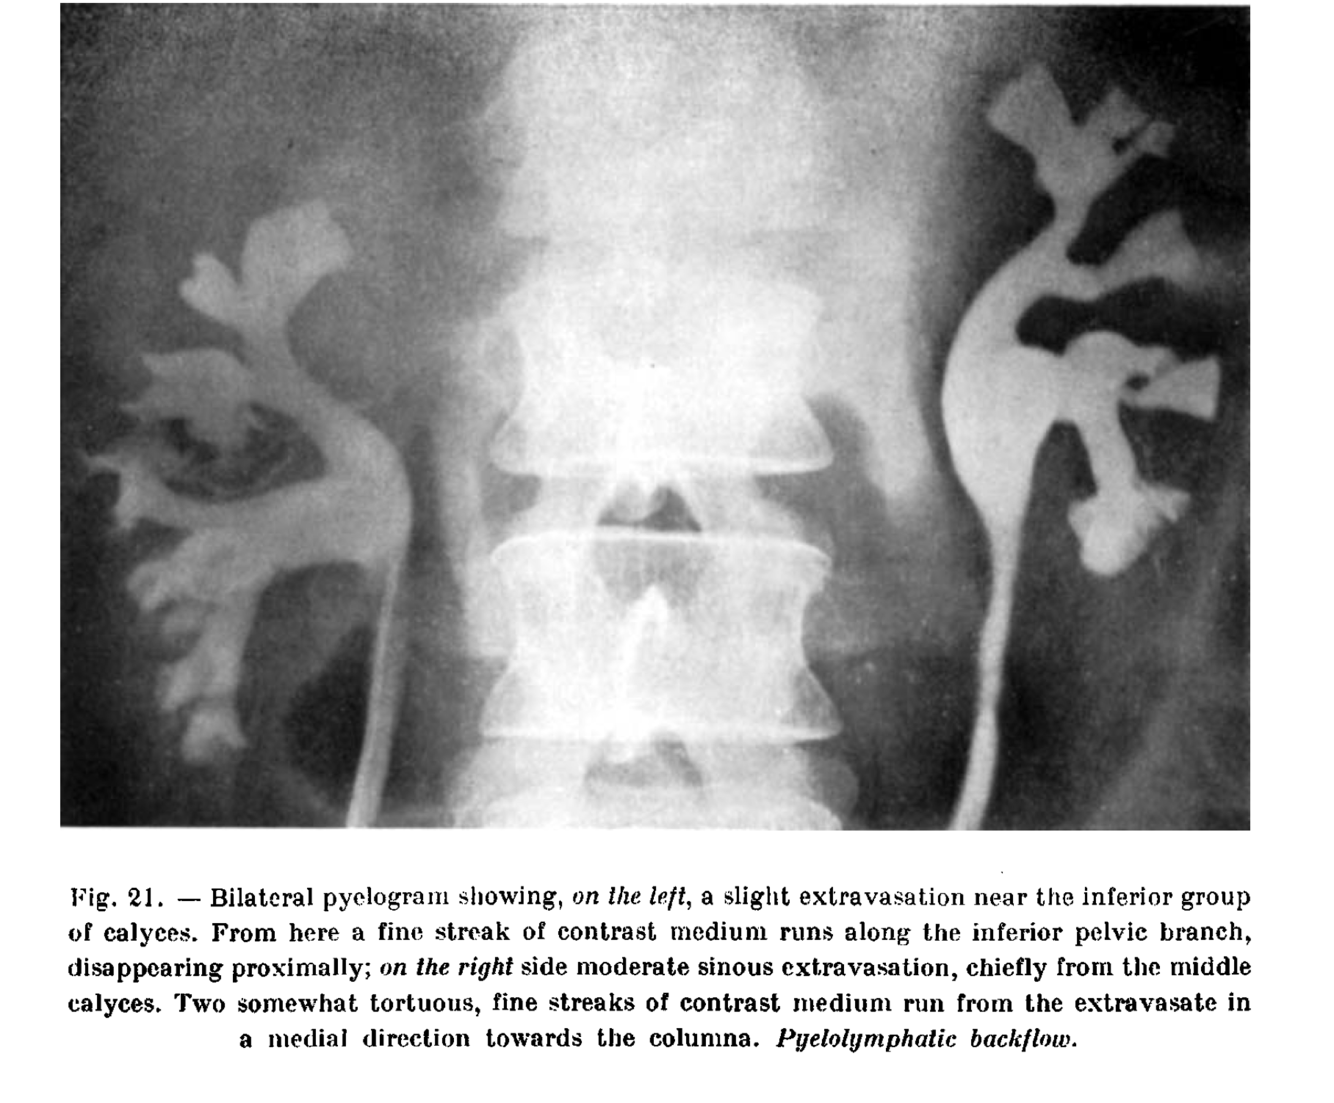

Pyelorenal Backflow

Backflow of contrast material from collecting system into renal or perirenal spaces. Usually caused by increased pressure in collecting system from retrograde pyelography or ureteral obstruction.

(lymphatic type)

https://www.tandfonline.com/doi/pdf/10.3109/00016925309175821